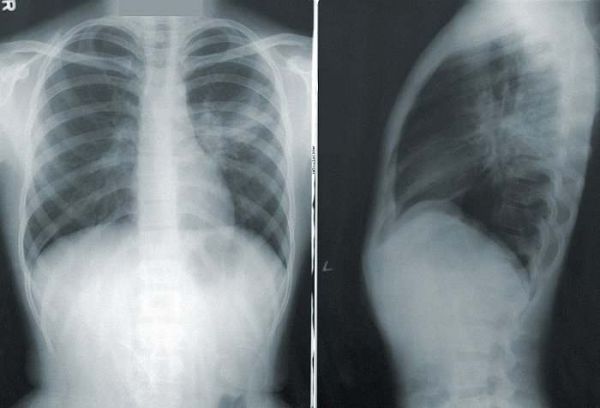

摆在医生们面前的,是一张肺部CT照片。

这张照片清晰、干净,影像轮廓与常人无二,即使是最具经验的放射科医生也会做出一致地判断:肺部健康,无异样。

但AI算法会得出不一样的结论:通过观察细微至人眼不可见的肺部斑点,它能判定这名病患已经呈现出早期肺癌的症状,应当及时治疗;如果放任不理,病情就将在未来的1~2年内,发展至能明显确诊的地步。

由谷歌联合西北大学等多所机构联合开发的这套算法有望解决肺癌患者的早期确诊难题。利用人工智能,AI模型能够以95%的准确率检测出患者胸部微小的癌症斑点,相比之下,传统的放射科医生的准确率约为65%。

这套AI模型能够根据患者胸部的CT图像,诊断出早期肺癌。在去年进行的一项对比研究中,与六位经验老道的放射科医生相比,AI的准确度更高,检测到的病例增加了5%,假阳性减少了11%,AUC达到94.4%。这意味AI模型能够更早、更准确地发现癌症病例,并且显著地减少了没有患肺癌的人被误诊的几率。